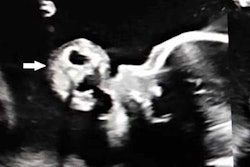

But a number of abnormalities were first identified on third-trimester ultrasound:

- Arachnoid cyst

- Duplex kidney

- Hydronephrosis

- Mild ventriculomegaly

- Ovarian cyst

- Ventricular septal defect